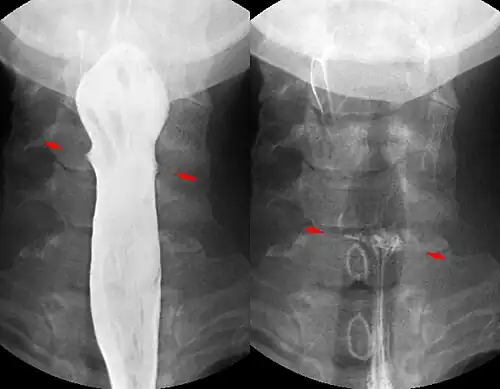

Contrast compounds containing barium or iodine, which are radiopaque, can be ingested in the gastrointestinal tract (barium) or injected in the artery or veins to highlight these vessels. The contrast compounds have high atomic numbered elements in them that (like bone) essentially block the X-rays and hence the once hollow organ or vessel can be more readily seen. In the pursuit of nontoxic contrast materials, many types of high atomic number elements were evaluated. Some elements chosen proved to be harmful – for example, thorium was once used as a contrast medium (Thorotrast) – which turned out to be toxic, causing a very high incidence of cancer decades after use. Modern contrast material has improved and, while there is no way to determine who may have a sensitivity to the contrast, the incidence of serious allergic reactions is low.[1]

X-rays are also used in "real-time" procedures such as angiography or contrast studies of the hollow organs (e.g. barium enema of the small or large intestine) using fluoroscopy. Angioplasty, medical interventions of the arterial system, rely heavily on X-ray-sensitive contrast to identify potentially treatable lesions.